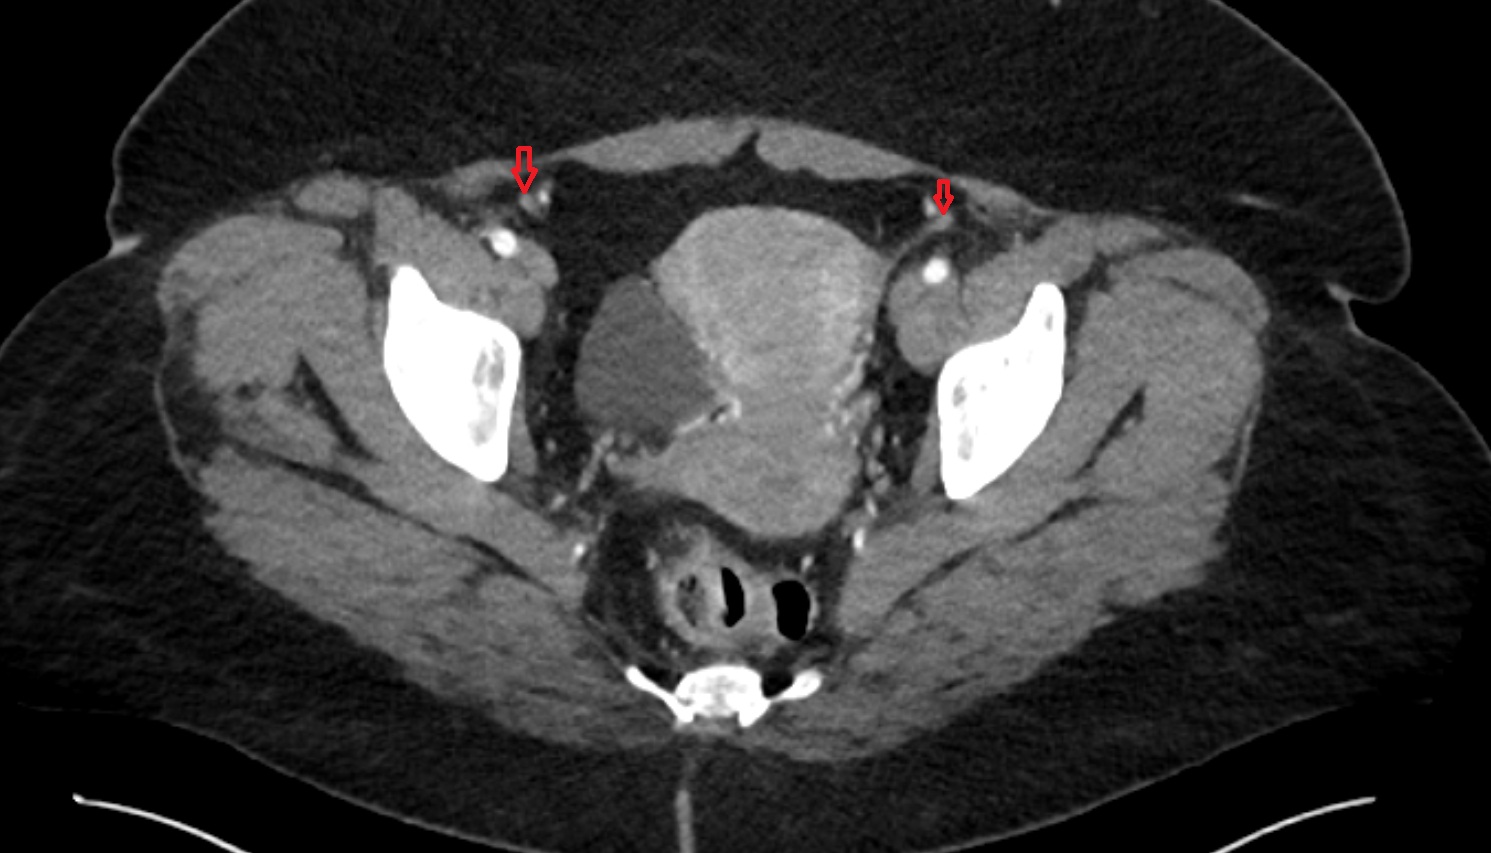

- Inguinal lymph nodes

- External iliac lymph nodes

- Obturator lymph nodes

- Superficial inguinal lymph nodes